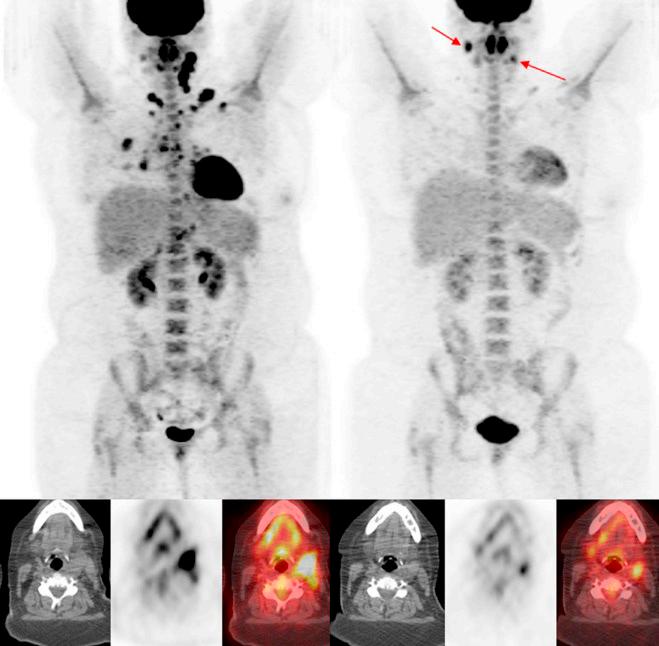

CT-scan of PET CT-scan

Deze test wordt gebruikt om te zien waar in het lichaam zich tumorcellen bevinden.

Een PET CT-scan is eigenlijk een combinatie van twee verschillende soorten scans, die worden “samengevoegd” om alles goed in beeld te brengen. PET staat voor “Positron Emission Tomography”.

Voor een PET-scan wordt gebruik gemaakt van fluorodeoxyglucose (FDG), een vorm van suiker met daaraan gekoppeld een licht radioactieve stof.

De meeste kankercellen hebben een verhoogde stofwisseling en verbruiken veel suiker. Door aan suikermoleculen een radioactieve stof te koppelen, kunnen kankercellen via een PET-scan zichtbaar worden gemaakt. (Met een PET-scan kan ook het ziektestadium worden bepaald, en kan worden nagegaan of de ziekte na een behandeling nog actief is).